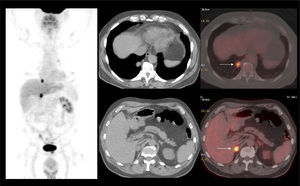

La vigilancia post tratamiento de un CCR suele ser prolongada, ya que las metástasis pueden aparecer varios años después de la cirugía (8). El PET/CT tiene especial valor en la detección precoz de dichas lesiones, permitiendo muchas veces plantear la opción de tratamiento quirúrgico curativo en algunos casos de oligometástasis (Figura 2).